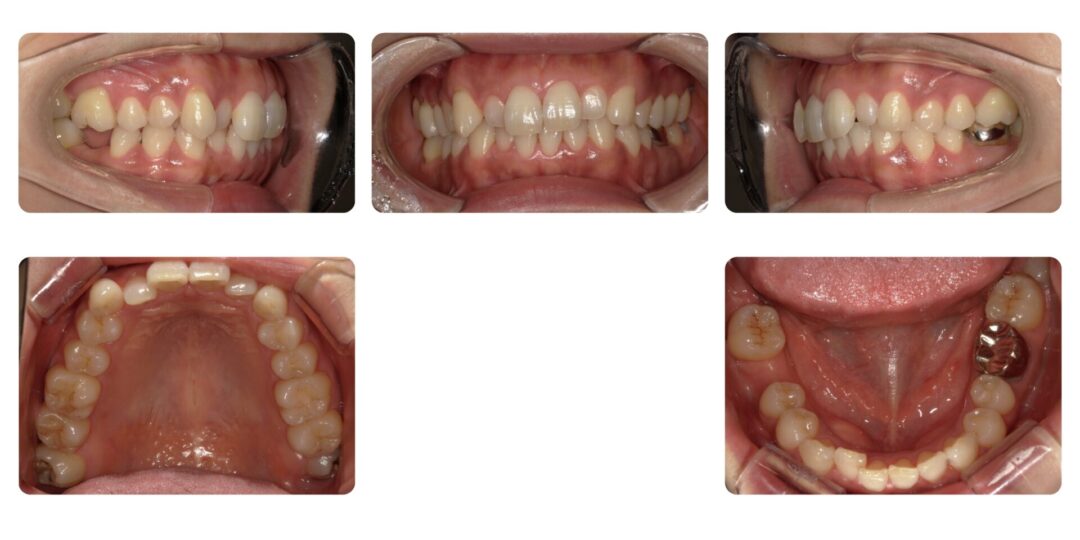

叢生を伴う歯槽性上顎前突|初診時38歳

矯正治療前